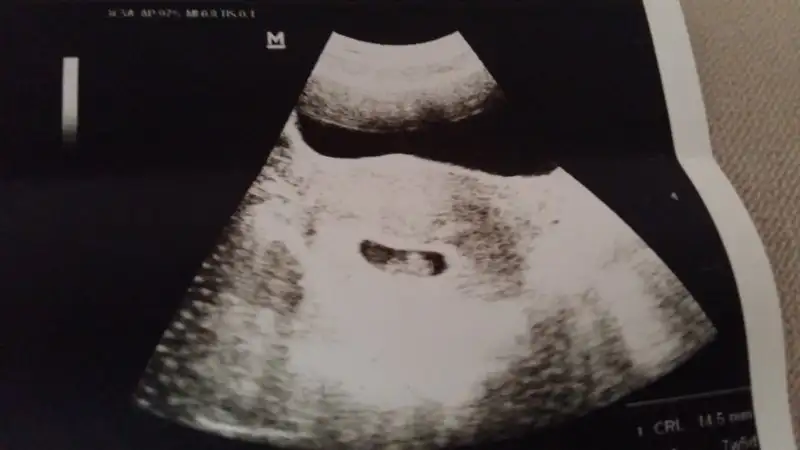

Kızlar dünden beri aklıma takıldı kesenin gergin olması diyorum hiç birşey bulamadım nette resme bakar mısınız normal gözükmüyor mu sizce

Eklentiler

• 1457536355901-1078323410.webp

1457536355901-1078323410.webp

10,4 KB · Görüntüleme: 97